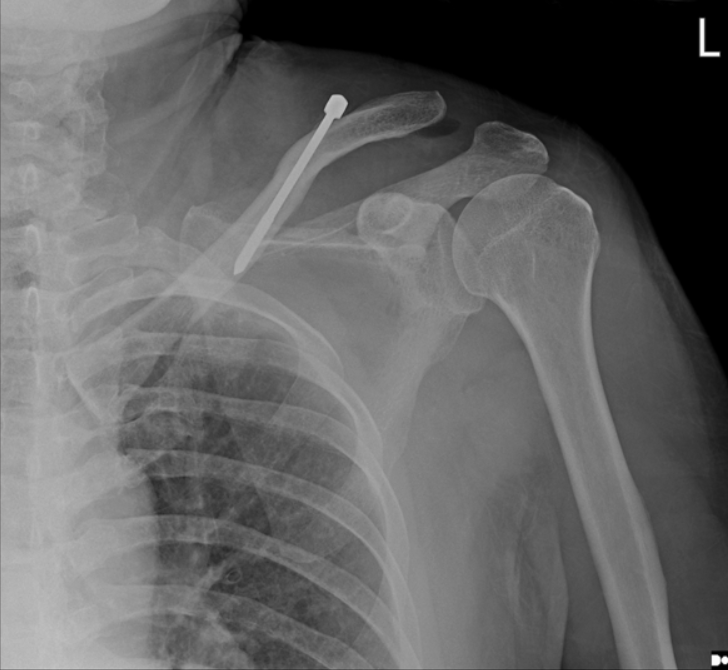

术后立即肩部x线片显示,锁骨骨折切开复位和Knowles针内固定后,肩锁关节(ACJ)明显移位。根据Rockwood分型诊断为V型ACJ脱位